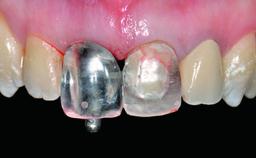

Replacement of a Failing Upper Left Central Incisor: Immediate Placement of an RC Bone Level Implant and Provisionalization

Loading Protocol Immediate

Retention Cemented, with prosthesis margin < 3mm submucosal Cemented, with prosthesis margin < 3mm submucosal

Provisional Implant-Supported Prosthesis Prosthodontic margin < 3 mm apical to mucosal margin Prosthodontic margin < 3 mm apical to mucosal margin